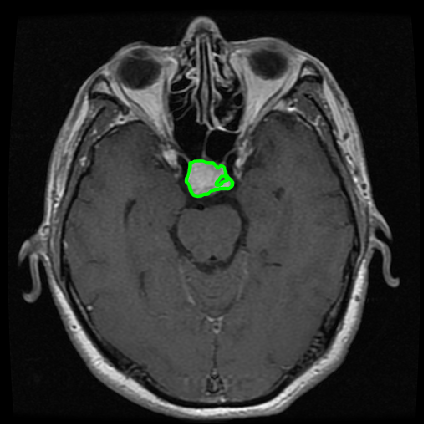

From the above discussions, we have discovered the significant potential of applying Retinex theory to image segmentation and explored its fundamental differences from traditional models. Traditional image segmentation models typically focus on the impact of intensity information on the segmentation results. Therefore, when faced with complex segmentation scenarios, the segmentation results are often affected by lighting, artifacts, and unclear boundaries in the image. As shown in Fig. 1, we present the results of the classical local model LIF [ZHANG20101199] for segmenting brain tumor images along with surrounding tissue edema. The irregular ring-like enhancement caused by the edematous tissue leads to irregular boundaries and low contrast in the images. Consequently, the LIF model can only identify the central necrotic and liquefied regions of the tumor, failing to detect the boundaries and becoming trapped in local minima. In this paper, we draw inspiration from the Retinex theory, which is widely applied in the field of image enhancement. According to Retinex theory, the reflectance component characterizes the intrinsic structural properties of the observed image and preserves texture information independent of illumination variations. By integrating this reflectance component into the level set framework, our model achieves robust segmentation of medical images even under severe intensity inhomogeneity. In addition, a linearized Structural-Prior is proposed to restore intensity consistency and capture local geometric features, thereby improving boundary localization in complex or blurred regions. Furthermore, a relaxed binary level set representation is employed to enhance robustness against noise and to enable accurate tracking of complex contours. Based on these innovations, we propose a novel variational reflectance-based level set model (RefLSM) that simultaneously corrects bias fields and performs segmentation. Experimental results demonstrate that RefLSM significantly outperforms conventional level set methods in both segmentation accuracy and robustness. We present the results of our model segmenting the two brain tumor images mentioned above in Fig. 2.

To address the challenge of segmenting images with severe intensity inhomogeneity, we propose a linearized structural prior that directly operates on the reflectance component . Reflectance-based structural information is more robust to illumination variations and bias field distortions, helping preserve weak edges and subtle anatomical boundaries. As shown in Fig. 2, our method can accurately delineate tumor boundaries and surrounding edema even under severe inhomogeneity, where traditional intensity-based models often fail. The proposed prior aligns smoothed reflectance gradients with data-driven directions, enhancing inter-region contrast, preserving weak edges, and stabilizing the evolution of . Formally, we define the linear structure operator as the gradient field of the smoothed reflectance: